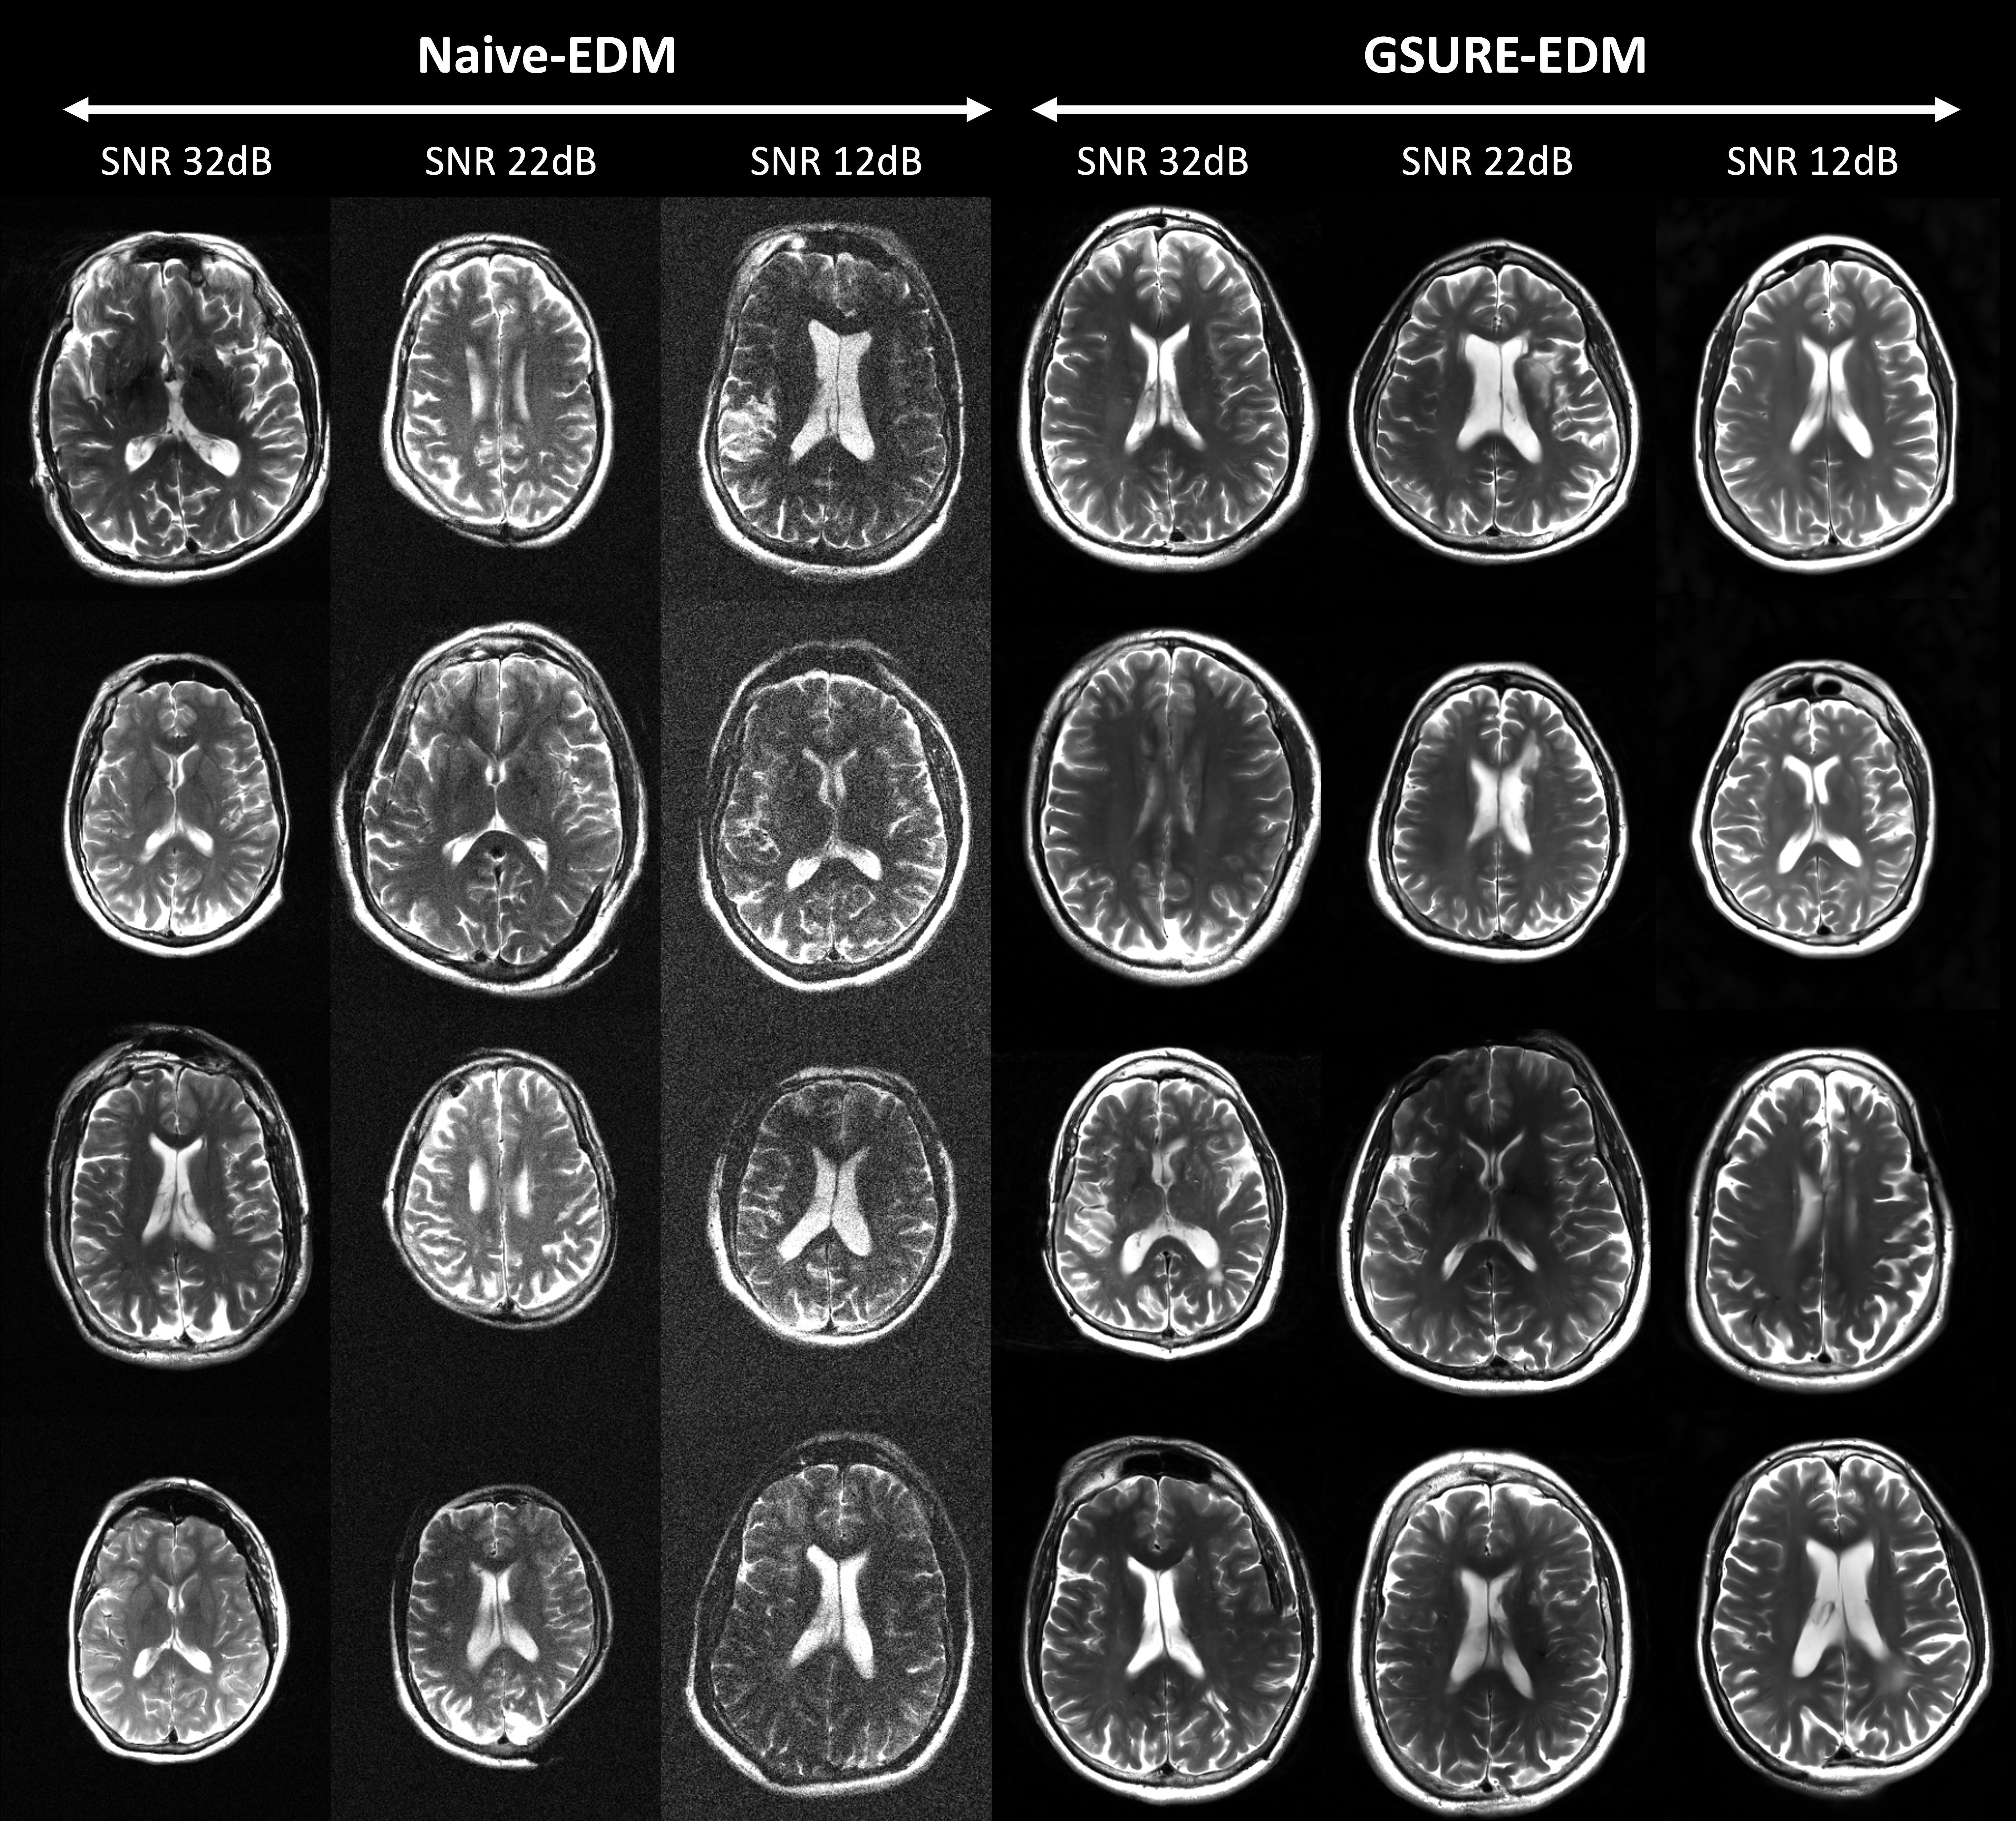

Refer to caption

Figure 2: Unconditional T2-Weighted Brain images generated from EDM models trained on two datasets: a) Noisy (Naive-EDM), and b) GSURE denoised (GSURE-EDM). Across each column, we show prior samples across three different training SNR levels. Across each row, we show different realizations of images generated from the same distribution. We can observe that GSURE-EDM consistently generates qualitatively superior images, notably at lower SNR levels.

Figures 2 and 3 show prior samples from GSURE-EDM and Naive-EDM across each anatomy and SNR level. GSURE-EDM models consistently produce higher quality priors than Naive-EDM models. As SNR decreases, GSURE-EDM models offer qualitatively more accurate and realistic approximations of the fully sampled native SNR data, while Naive-EDM models retain noise.